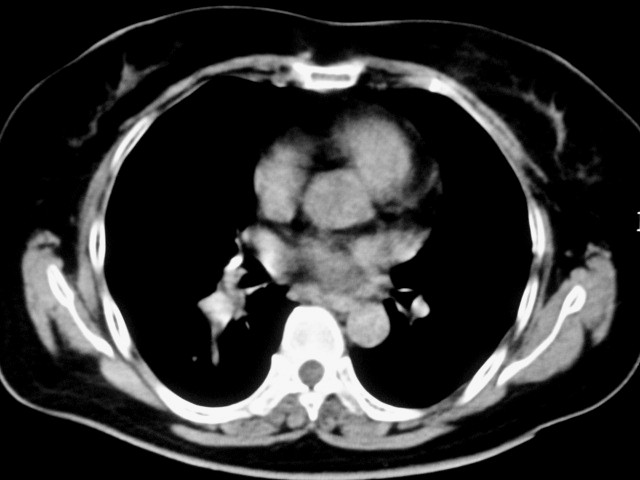

以下是引用清清楚楚在2007-8-28 7:13:00的发言:[br]右肺下叶可见斑片状高密度影,边缘模糊;右肺中叶内侧段及左肺舌段亦可见小斑片状模糊影。[br]考虑双肺感染,建议抗炎治疗后复查。

以下是引用天南地北在2007-8-27 23:49:00的发言:[br]右肺下叶可见斑片状高密度影,边缘模糊;右肺中叶内侧段及左肺舌段亦可见小斑片状模糊影。[br]考虑双肺感染,建议积极抗炎治疗后复查。

以下是引用难听在2007-8-28 13:17:00的发言:[br]右肺下叶背段支气管狭窄,是否可以考虑新生物伴阻塞性肺炎.请大家帮帮忙,这个病人是卫生局长的丈母娘.惹不起啊.